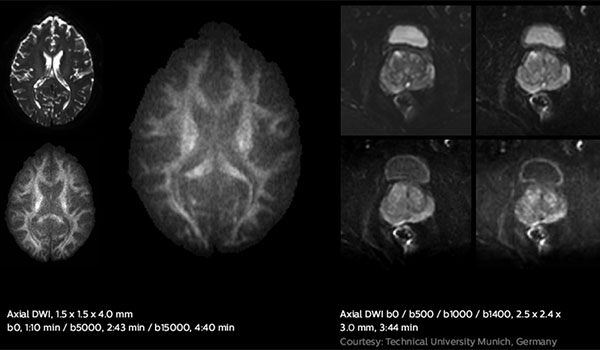

Fast diffusion scans